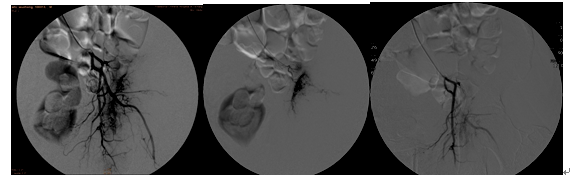

典型病例一、

患者、男、53岁,前列腺癌左髋关节转移剧烈搏动性疼痛,关节不能伸直,行左侧转移瘤相关血管栓塞术后患者疼痛消除。